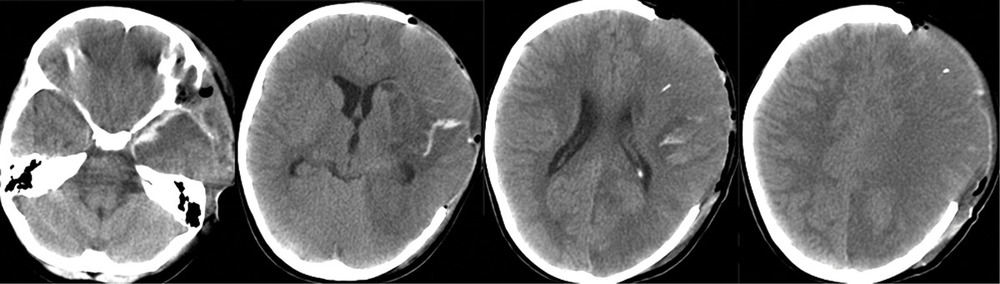

На 3-и сутки, несмотря на проводимую седацию и обезболивание, отмечалось устойчивое повышение ВЧД до 30 мм рт.ст. Гиперосмолярная терапия, гипервентиляция и углубление седации приводили лишь к кратковременному эффекту. Впоследствии развилась гипернатриемия — Na плазмы крови колебался в пределах 155—165 ммол/л. По данным ТКДГ, отмечалось нарастание скорости кровотока: пиковая ЛСК по СМА слева — 300—310 см/с, справа — 200—220 см/с. В связи с отрицательной динамикой состояния была выполнена КТ головного мозга (рис. 3),

при которой отмечены выраженный отек и формирование обширного очага ишемии в левом полушарии. Желудочковая система и базальные цистерны прослеживались. Для проведения дифференциальной диагностики вазоспазма и постдислокационных нарушений кровообращения была выполнена прямая ангиография, по результатам которой выраженный ангиоспазм в левом каротидном бассейне не был подтвержден (рис. 4).